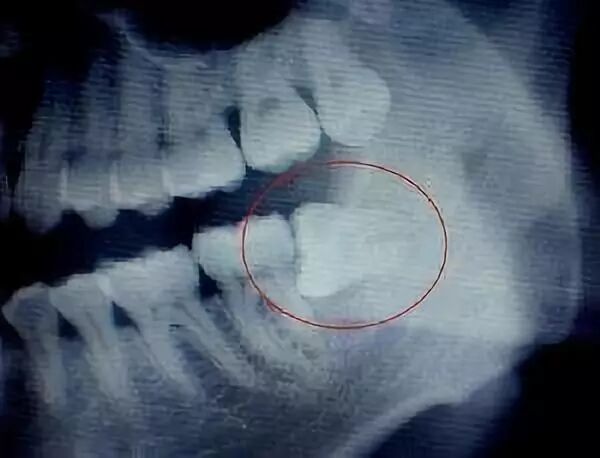

智齿的形态也是各种各样,简单可以罗列如下几种,实际复杂远不止以下

但有一些智齿,它是倾斜长的,或者是水平长的,或者是埋在骨头里的,甚至压着神经管的,这时候就需要将软组织切开,做周围骨头的去除; 也有一些,为了尽量少去骨,而进行微创手术拔除的,需要把智齿切割成一小块一小块,然后逐块取出,这种智齿拔除手术的难度和对医生的操作要求都相对较高,因此价格也会相应地提升。 综上所述,拔除一颗智齿需要花多少钱,还需要根据这颗智齿拔除的难易程度以及患者口腔的具体情况而定。